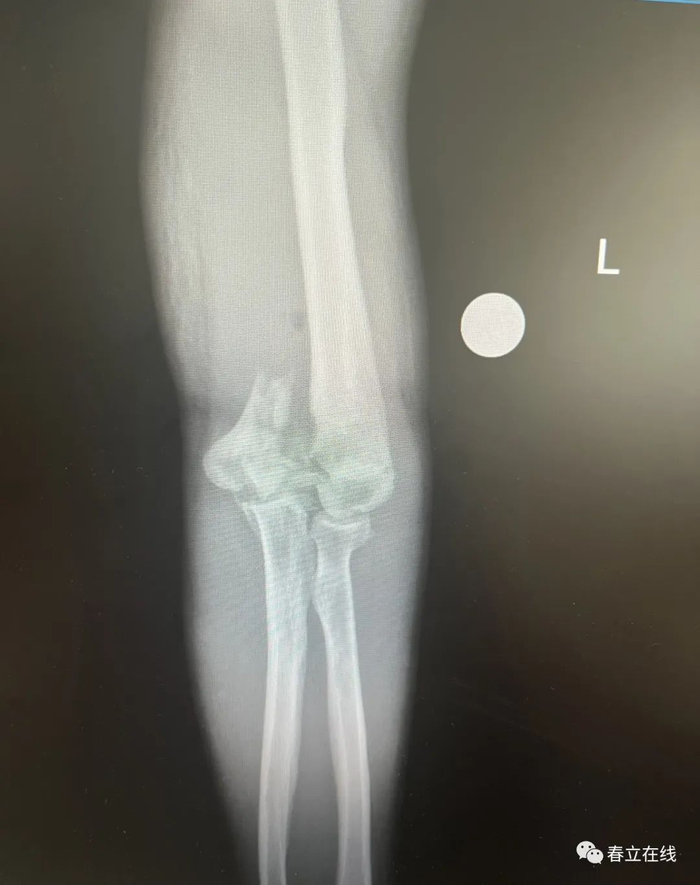

【行X线检查提示】1、左肱骨下端粉碎性骨折;2、左侧尺骨未见异常。

【初步诊断】1、开放性多发性前臂骨折;2、开放性肱骨骨折。